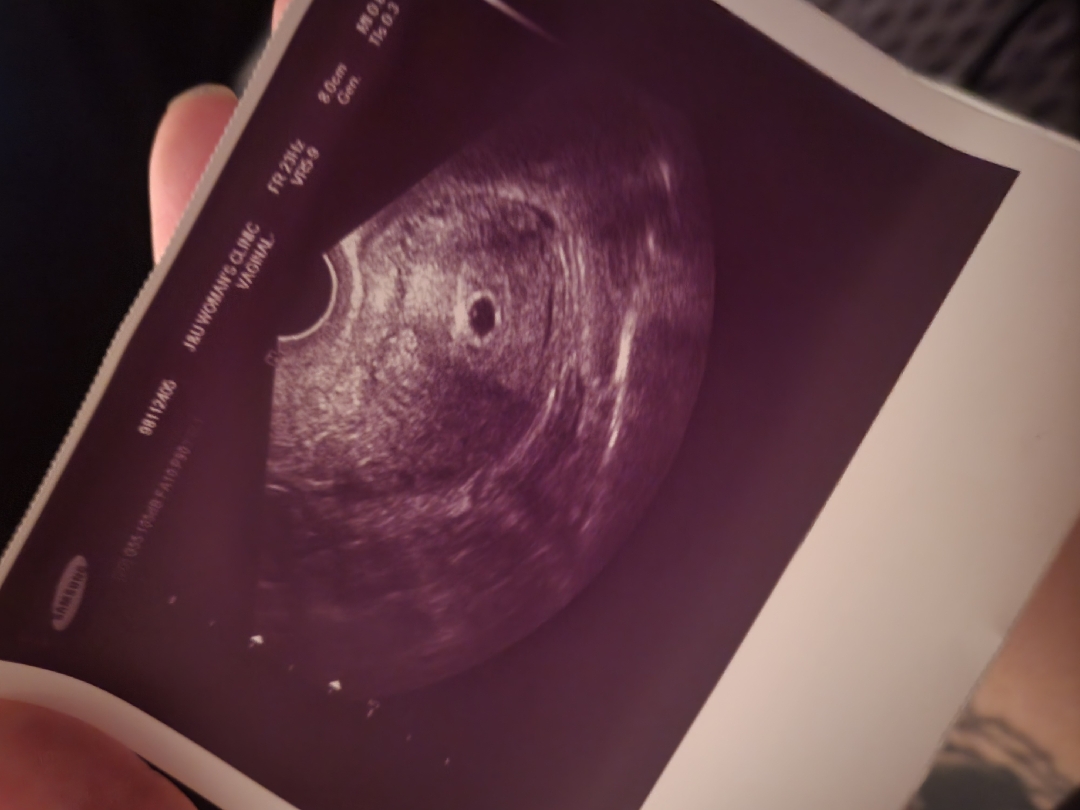

위에사진이 <8월1일> 초음파 에요 7월29일날 초음파보러 갔을때는 아기집이 아직 안생겼다고 며칠뒤에 오라해서 8월1일날 갓는데 아기집이랑 난황 보고왔어요! 댓글사진이 8월7일인데 병원에서 8월1일 초음파랑 크기가 거의 변함이없다구 ..ㅜㅜ 8월7일이 6주3일이였는데 초음파상으론 5주4일로되엇어요ㅜ 막생이 시작이 6월24일인데 원래 생리가불규칙햇어요 처음에 아기집안보엿을때 의사선생님께서 늦게 배란.착상됫을수도 잇다고햇거든요..ㅜ 이번주에 분만병원가서 꼭 심장소리 들으라고하시더라고요 저번주랑 비해서 너무 비슷해서 자연유산일확률도있다고..ㅜㅜ 불안하네요ㅜㅜ 내일이나 모래 병원가려구용..